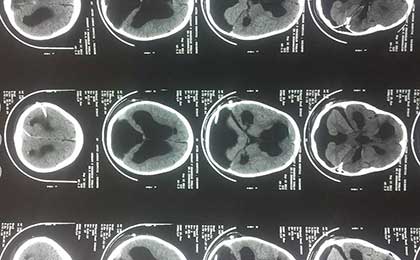

post op ct

• post op ct